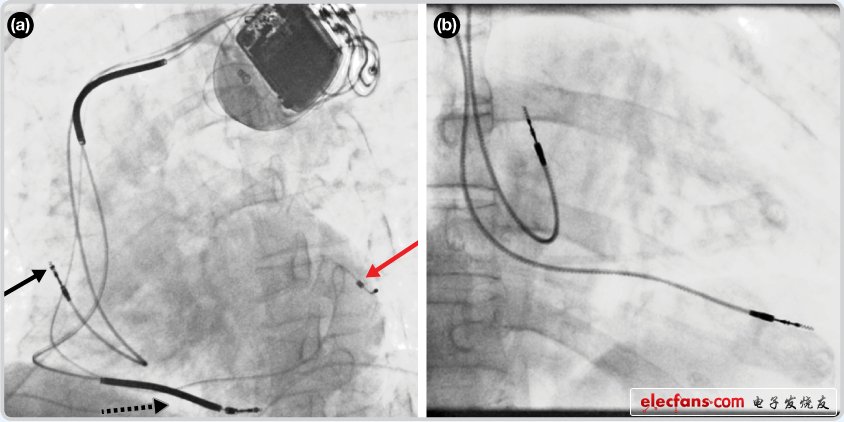

CRT器件在图4(a)中的透视图像中可以看见。医师就是利用这种影像来放置导联线的。对于非专业人士来说,这种影像是很难解读的。可以看到心脏淡淡的轮廓——这是搏动中的心脏的静态视图。起搏器位于右心房上,心脏顶点指向右下方。在这个典型的导联线放置实例中,黑色箭头指向右心房导联线。虚线黑色箭头指向右心室导联线。红色箭头标示的导联线只能看到一部分,这是左心室导联线(红箭头指向电极尖端)。图4(b)展示的是双腔起搏器的典型导联线放置透视图像。右心房导联线指向上方,置于右心房中。右心室导联线则位于右心室顶部。

图4. 起搏器导联线放置的透视图像3

(a)。 单腔起搏器;(b)。双腔起搏器